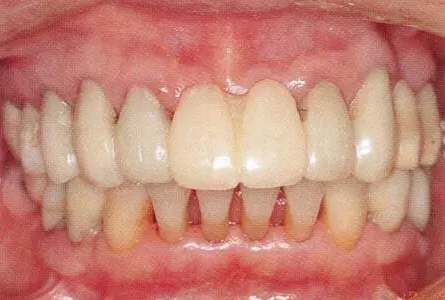

33333.png

▲圖19-13

佩戴最終修復(fù)體時的正面照片。